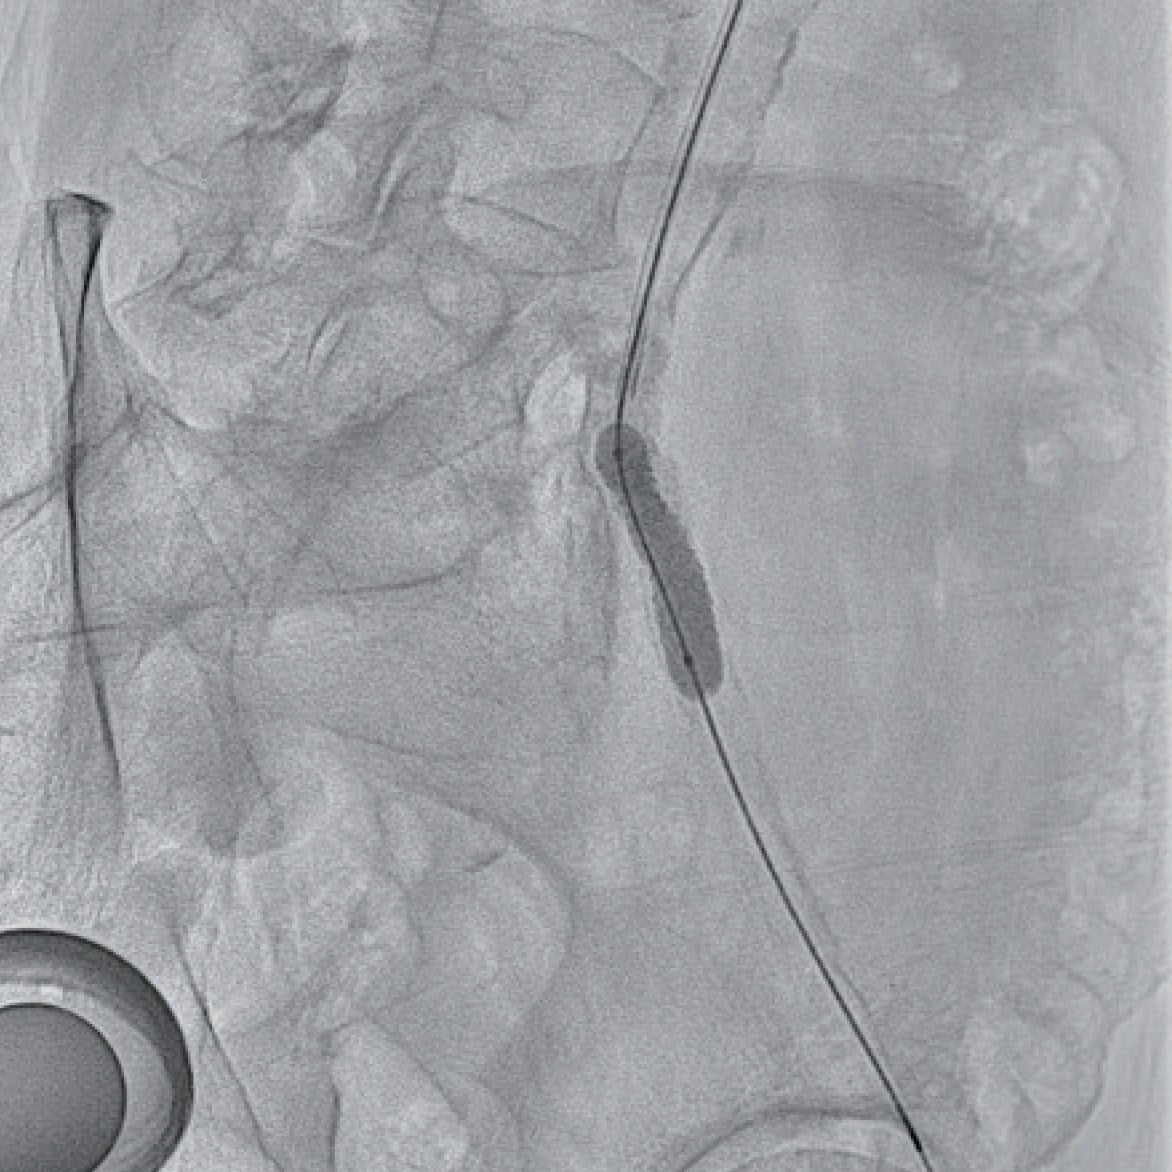

6 Frガイディングシースに変更しガイディングシースを左総腸骨動脈まで進めた。ガイドワイヤー通過は困難であったが、何とか0.014 inchガイドワイヤーを通過させて(図1b)、小径のバルーンで拡張後、IVUSで病変を評価した(図2)。全周性の表在型石灰化病変であり、通常のベアメタルステントでは拡張できないことが想定され、また内腸骨動脈との分岐部直下に置けるため、ステントグラフトの適応と判断した。6.0 × 40 mmのバルーンで拡張後、6 Frシステム対応のVBX ステントグラフト7.0 × 39 mmを留置、8.0 × 40 mmのバルーンで後拡張を実施(図3)した。IVUSで十分な血管内腔の確保を確認し(図4)、最終造影を行い、治療を終了した。穿刺からシース抜去までの手技時間は38分で、患者は車椅子で退室し、ベッド上の安静時間はゼロであった。足関節上腕血圧比(ABI)は術前の0.70から1.02まで上昇した。